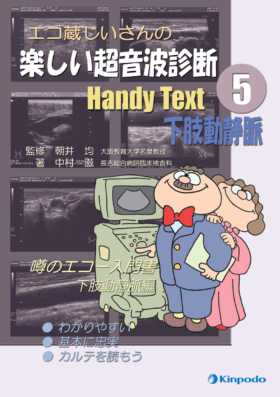

標準下肢静脈エコー【動画を含む電子版付】 松尾 汎(著/文 | 編集) - 日本医事新報社 | 版元ドットコム, Handy Text ⑤下肢動静脈 - 株式会社 金芳堂,

Handy Text ⑤下肢動静脈 - 株式会社 金芳堂, PVX Ver.2|精密超音波厚さ計|ダコタ・ジャパン,